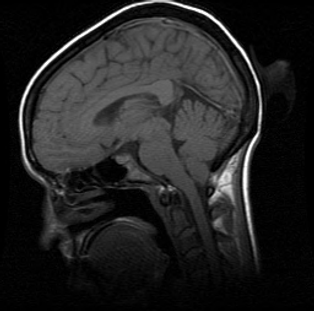

Que es ?

Es una malformación congénita que se caracteriza por varias anomalías estructurales del Sistema Nervioso Central. La más llamativa y que determina en general el motivo de consulta es la herniación de una porción de cerebelo, las amígdalas cerebelosas, a través del foramen magno provocando de esta manera la compresión del bulbo raquídeo y el sufrimiento de los nervios craneanos que se originan en él.